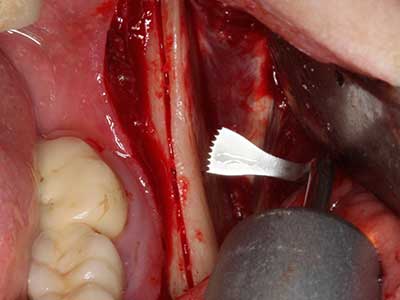

Когато се извършват хирургични процедури върху кост в непосредствена близост до чувствителни структури като кръвоносни съдове или нерви, ротиращите инструменти създават значителен риск за ятрогенно нараняване. Пиезоелектрическите апарати могат да бъдат от помощ при препарация на костно покритие и отстраняване на твърда кост близо до нерви, особено за оголване на нервите след ятрогенно нараняване, както и по време на латерализация на нервите за резекционни и реконструктивни процедури или поставяне на имплант (Фиг. 17-20). Лекият контакт между пиезонакрайника и нерва по принцип не води до нараняване, но ако действате непредпазливо с трионообразни движения или приставки за остатъчен костен субстрат, може да причините временно или перманентно увреждане на нерва. Въпреки това, рискът от увреждане се счита за много по-малък, отколкото при употреба на триони или ротиращи инструменти (Pereira, Gealh et al. 2014).